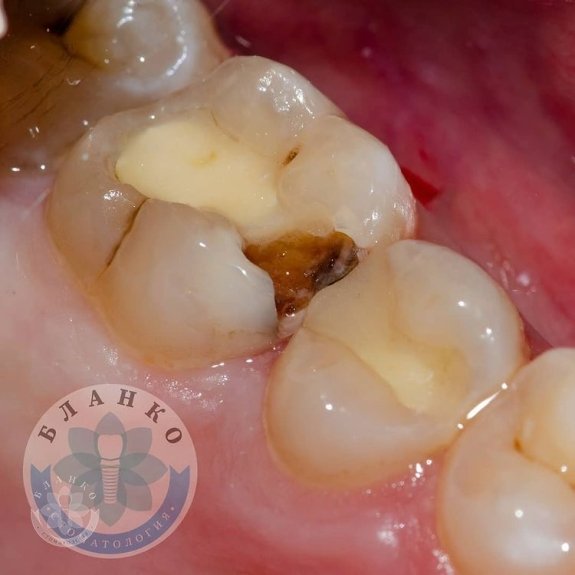

🔹На фото острый (местами хронический) глубокий кариес 🔹

— Ещё б немножко и дело дошло бы до лечения каналов, что дольше и дороже, а самое главное намного хуже для зуба.

⌛️Вовремя обратился и мы вылечили кариес на долгое время с помощью установки пломбы ( реставрация зуба ). 🖇Так же хотим обратить внимание на контактный пункт ( место где два зуба встречаются друг с другом ),если его плохо восстановить то между зубами постоянно забивается еда и воспаляется десна 🥵